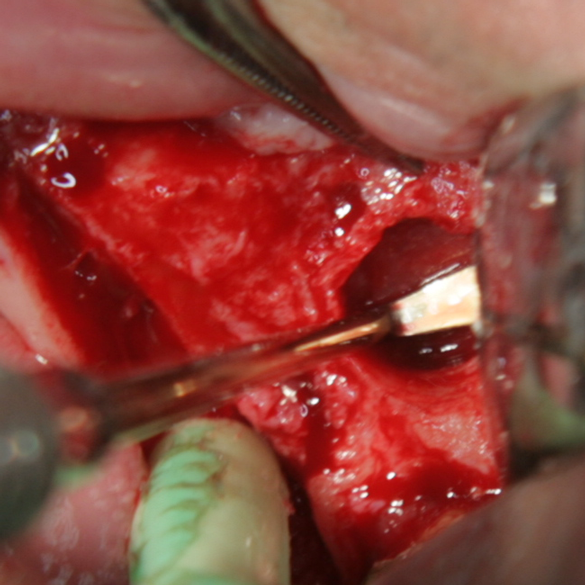

Отворен максиларен синус в началото на интервенцията. Случаят е интересен със следното - твърде атипична форма на трепанационния отвор. На какво се дължи на това - на лошо планиране на оперативния достъп или на нещо друго? Дължи се на факта, че отначало въпросната намеса беше планирана като балонен синуслифт; за съжаление обаче мембраната на синуса се разкъса и надуването на балона стана невъзможно.